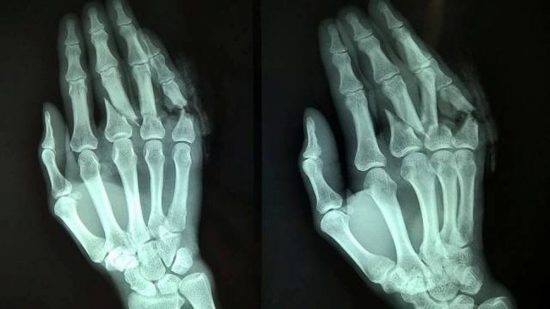

Trên đây là một số bệnh lí thường xuyên gây ra biểu hiện đau, sưng, tê ở các ngón tay và bàn tay. Để có chuẩn đoán chính xác, người bệnh nên đến các cơ sở khám chữa bệnh làm thêm các xét nghiệm cận lâm sàng như công thức máu, X-Quang, Scan,...